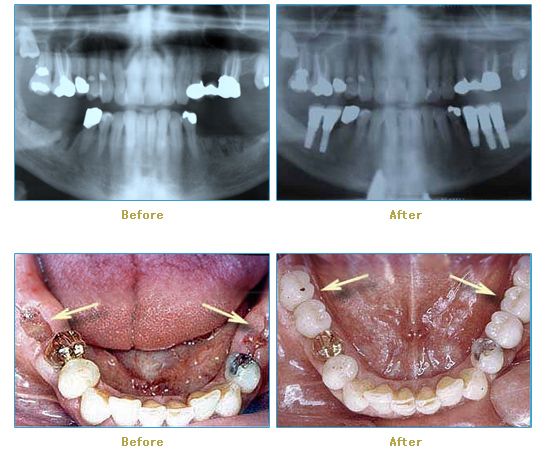

Dr. Cabianca has restored hundreds of smiles through the latest techniques in restorative and cosmetic dentistry. The following before and after photos document a few such cases in which Dr. Cabianca has replaced and reshaped teeth to produce wonderful smiles. Click on any of the images below to view larger versions of the photos.